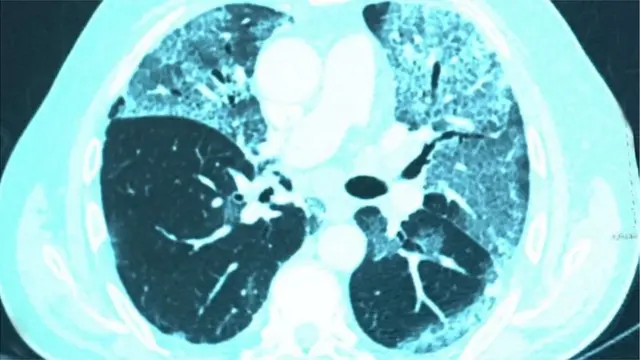

কোভিড-১৯ নামের এই রোগে প্রধানত ফুসফুস আক্রান্ত হয়।

বক্ষব্যাধি বিশেষজ্ঞ ডা. রওশন আরা খানম বিবিসি বাংলাকে বলছেন, ''করোনাভাইরাসে আক্রান্ত হওয়ার পর যাদের হাসপাতালে ভর্তি হতে হয় বা আইসিইউতে যেতে হয়, তাদের ফুসফুসের ক্ষতিটা বেশি হয়। তাদের সেই ক্ষতি কাটিয়ে উঠতে, স্বাভাবিক জীবনযাপনে যেতে অনেক সময় লেগে যায় বলে আমরা দেখেছি। তাদের জন্য পরবর্তীতে 'ফুসফুসের পুনর্বাসন প্রোগ্রাম' দরকার হয়ে পড়ে।''

বক্ষব্যাধি বিশেষজ্ঞ ডা. রওশন আরা খানম বলছেন, করোনাভাইরাসে আক্রান্ত হলে মানুষের শরীরে অনেক সময় অক্সিজেনের স্বল্পতা তৈরি হয়। ফুসফুসের কার্যক্ষমতা কমে যাওয়ার কারণেই এটা হয়।